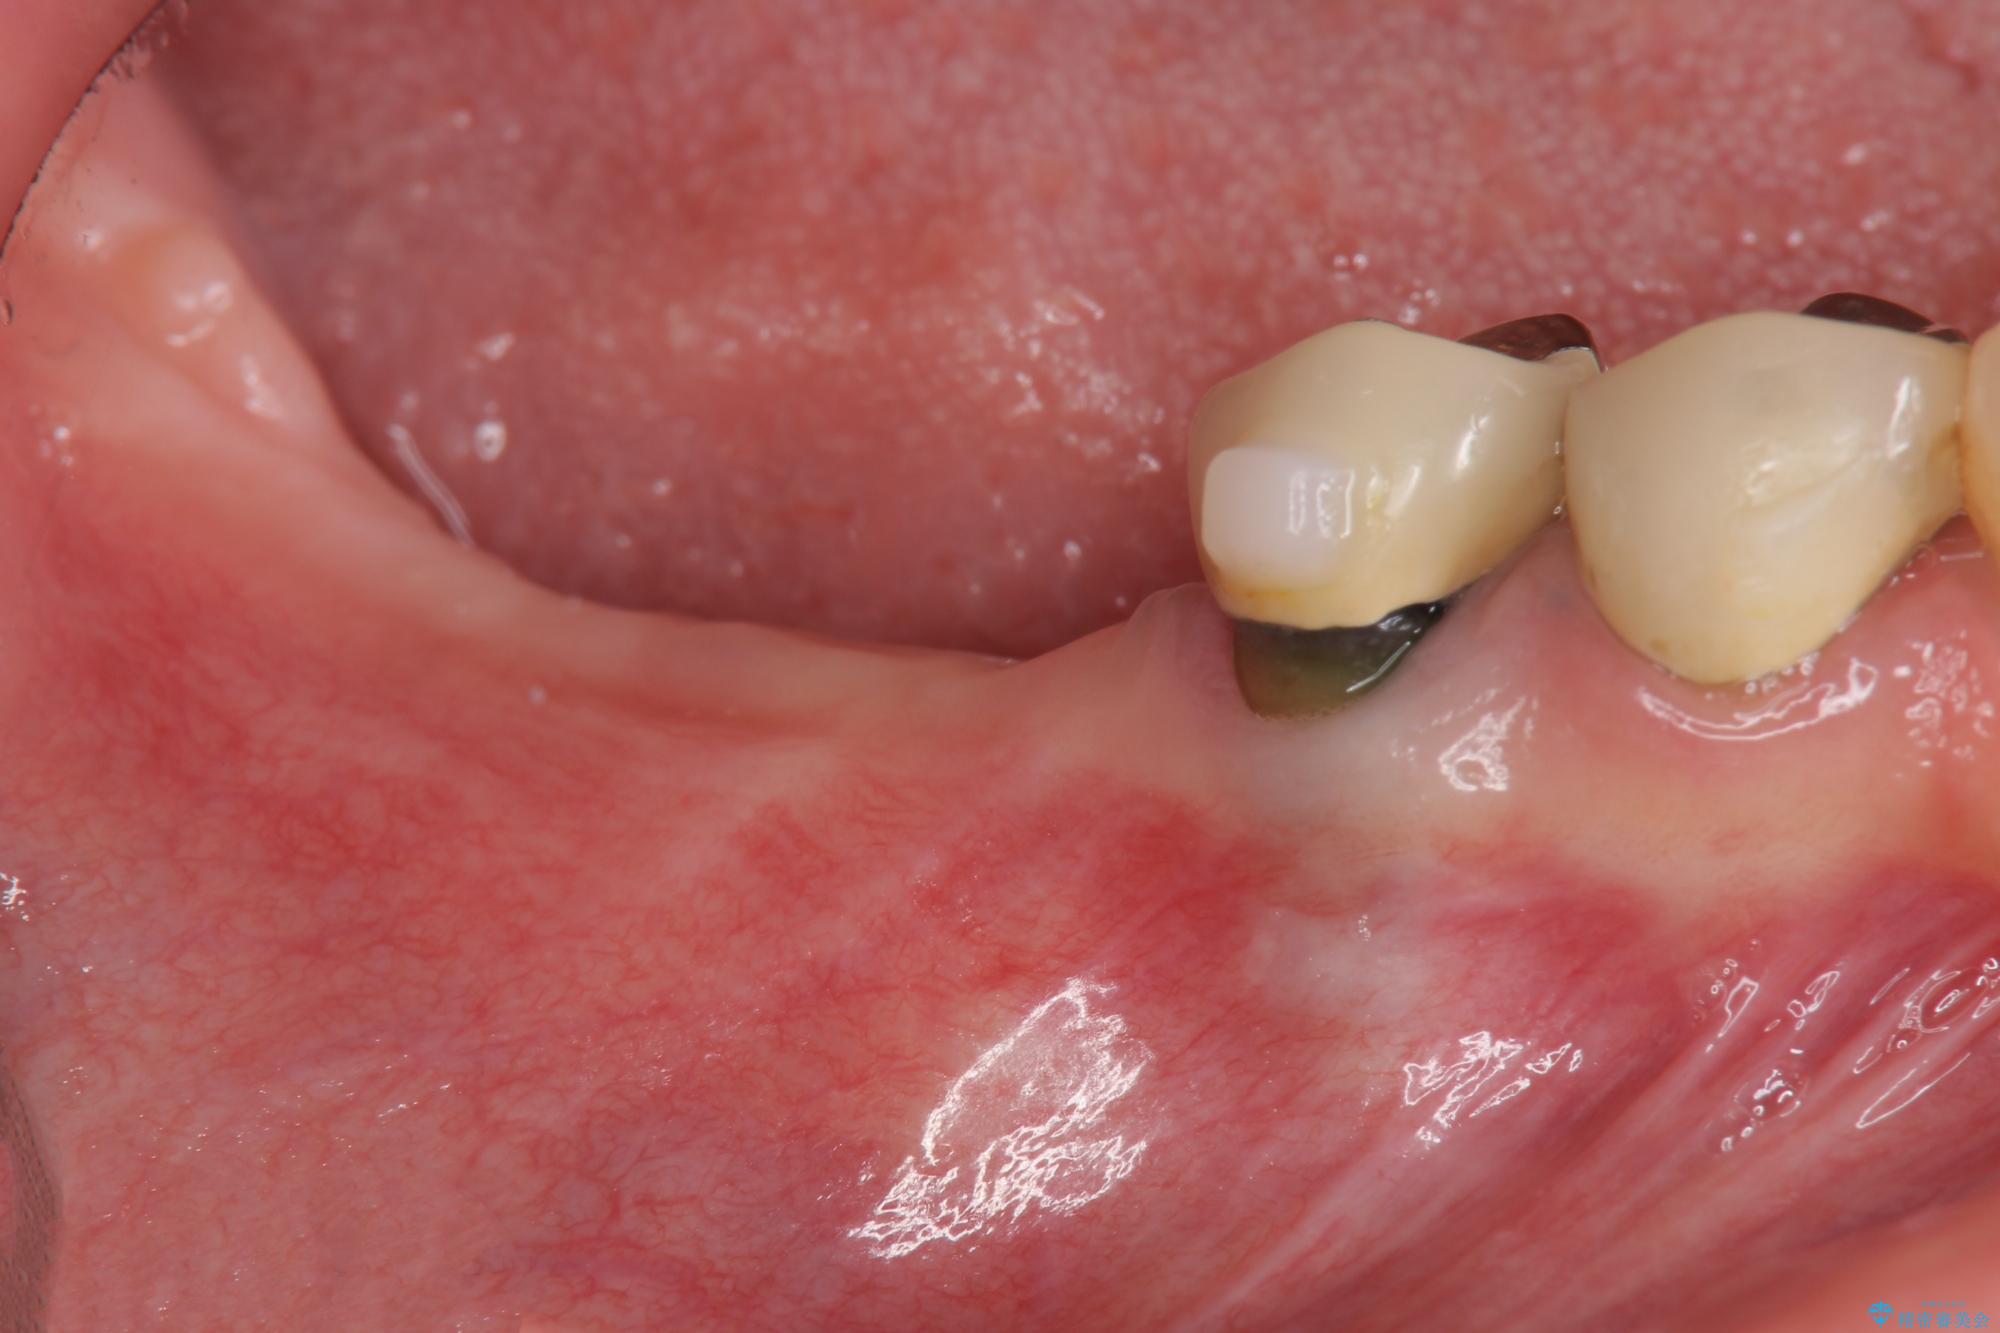

治療前

遊離歯肉移植術を伴うインプラント治療 治療前画像 遊離歯肉移植術を伴うインプラント治療 治療前画像 遊離歯肉移植術を伴うインプラント治療 治療前画像 遊離歯肉移植術を伴うインプラント治療 治療前画像 遊離歯肉移植術を伴うインプラント治療 治療前画像 遊離歯肉移植術を伴うインプラント治療 治療前画像 遊離歯肉移植術を伴うインプラント治療 治療前画像 遊離歯肉移植術を伴うインプラント治療 治療前画像 遊離歯肉移植術を伴うインプラント治療 治療前画像